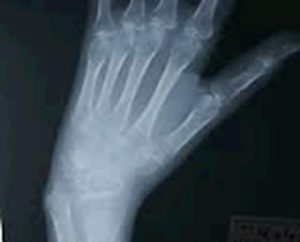

XPによって、関節軟骨や骨質が保たれたまま高度な骨萎縮を認めます。

つまり、骨がスカスカになっている状態がみてとれるのです。

足指の基節骨、末節骨が黒ずんで見えますが、これがSudeck骨萎縮です。